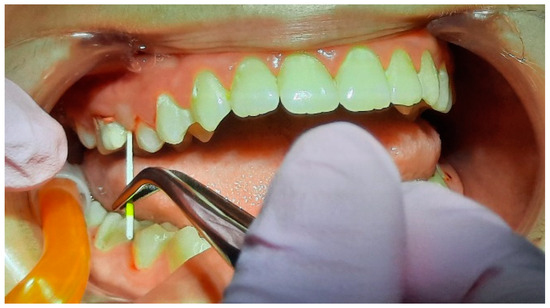

2.2. Clinical Examinations

2.3. Sampling for PCR

2.5. Specialist Treatment

3.2. Analysis of Clinical Data